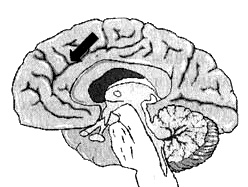

Поясная извилина

Иллюстрация к книге — Измените свой мозг - изменится и жизнь! [i_055.jpg]

Глубоко в центральной части мозга, вдоль лобных долей, проходит поясная извилина. Это та часть мозга, которая позволяет вам переключать внимание с одного объекта на другой, переключаться с одной мысли на другую, видеть различные варианты решений.

Считается, что она отвечает и за ощущение безопасности.

На мой взгляд, точнее всего функции этой области мозга можно выразить термином «когнитивная гибкость».